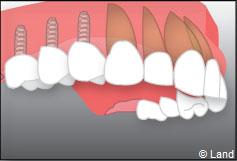

Exemple d’un implant unitaire pour remplacer une dent antérieure manquante.

– le remplacement d’une dent unitaire. Grâce à ce procédé, il n’y a pas de mutilation des dents voisines.